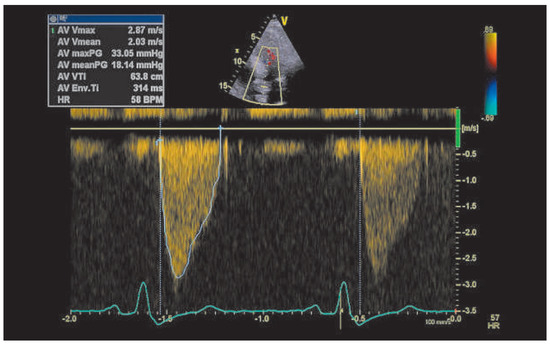

Late Transcatheter Aortic Valve Thrombotic Obstruction

by Simon Andreas Müggler, Sabrina Gisler-Jantzen, Jörg Gasser and David Tüller

Cardiovasc. Med. 2015, 18(7-8), 222; https://doi.org/10.4414/cvm.2015.00347 - 12 Aug 2015

Viewed by 144

Abstract

Late valve thrombosis is uncommon after transcatheter aortic valve implantation. Herein, we describe such a complication after transcatheter aortic valve implantation of an Edwards SAPIEN XT aortic bioprosthesis valve. Full article

Show Figures

Figure 1